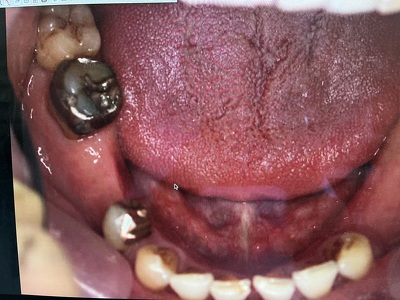

初診より8年後の下顎の写真